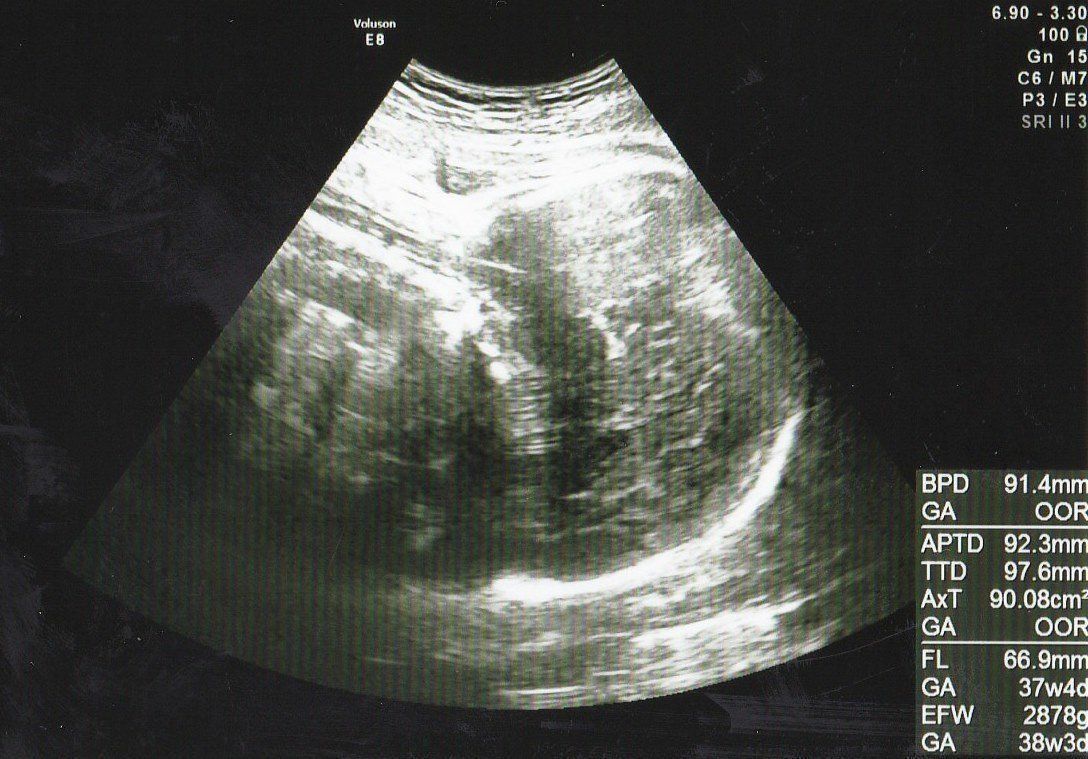

妊娠36週目エコー写真 「もう生まれても大丈夫」と、先生からお墨付き

推定体重=2878g

右側に頭、体は背中を向けて左側に、手を顔の前においているエコー画像です。赤ちゃんの体重はもうすぐ3kgというところ。先生から「(大きさとしては)もう生まれても大丈夫」と言われましたが、陣痛などの兆候は全くなく、出産がいつか、いつかとそわそわしていました。

順調に進んでいった妊娠生活でしたが、最後に波乱が待っていました。日課にしていたお散歩中に破水し、即入院。陣痛促進剤で誘発するも子宮口は開かず、破水から48時間経過して「感染症の恐れが高まる」と説明を受け、緊急帝王切開による出産に切り替えられました。

38週0日で出産したわが子は体重3108g、身長51.0cmのまるまると太った元気な男の子。予想していなかった帝王切開になりましたが、母子ともに健康で、元気に退院することができました。「無事に生まれてきてくれてありがとう」と心から感謝しています。